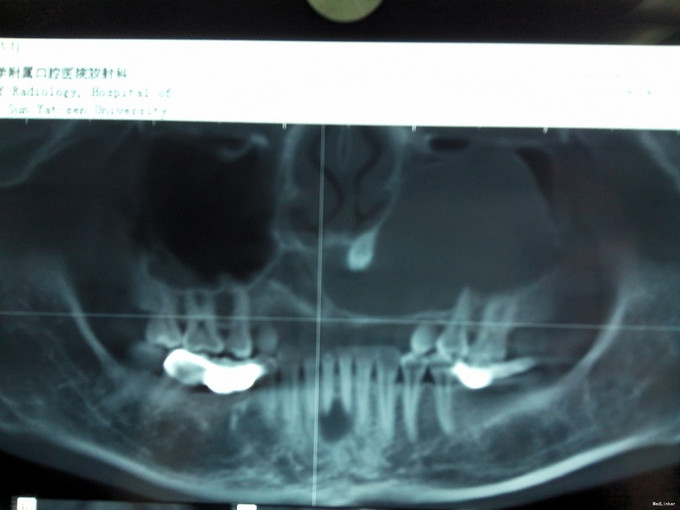

检查:口外检查:左侧鼻唇沟区轻微隆起,鼻唇沟较右侧稍浅,表面皮肤无红肿破溃,无明显压痛,无乒乓球样感。 口内检查:左上颌唇侧前庭沟轻微隆起,触诊无乒乓球样感及波动感,无压痛,腭侧未见明显骨质膨隆,41舌侧牙色充填物,31,41叩(±),松(I),冷热测无反应,牙髓活力测试无活力,牙龈正常,余牙及粘膜未见明显异常。 辅助检查:外院全景片示11至28根尖区可见一明显类椭圆形透射影,边界较清,约6.0*4.0cm大小,其内含一多生牙牙冠,41根管内致密充填影像,31,41 根尖周可见小范围低密度影. 全景片及CBCT片如图

诊断:1.左上颌骨囊肿:含牙囊肿? 2.上前牙去多生牙 3. 31,41慢性根尖周炎 治疗方案:1.全麻下行左上颌骨囊肿刮除术+上前牙区埋伏多生牙拔除术, 2.术后择期治疗下前牙 治疗: 常规全麻消毒铺巾,切开翻瓣,颌骨开窗,显露囊肿,见囊肿壁薄,囊壁已破溃,灰褐色豆渣样物质,剥离囊肿,拔除多生牙,冲洗,妥善止血,缝合。术后病理结果示左上颌骨含牙囊肿。转诊牙体择期治疗下前牙。